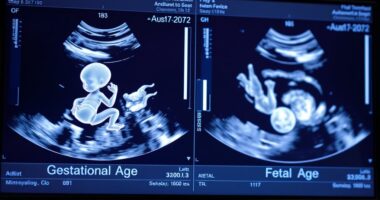

Oligohydramnios, which is marked by low levels of amniotic fluid during pregnancy, can pose serious risks for both you and your baby. This condition affects about 4% of pregnancies and can stem from various causes, such as placental issues, premature rupture of membranes (PROM), or maternal health conditions like hypertension and diabetes. Diagnosing oligohydramnios typically involves ultrasound assessments to measure the volume of amniotic fluid, allowing healthcare providers to monitor your situation closely.

To diagnose oligohydramnios, your doctor typically uses an ultrasound to measure the amniotic fluid volume.

They calculate the Amniotic Fluid Index (AFI) or assess the Single Deepest Pocket (SDP) of fluid. If the AFI is 5 cm or less, or if the SDP is under 2 cm, you might be diagnosed with oligohydramnios.